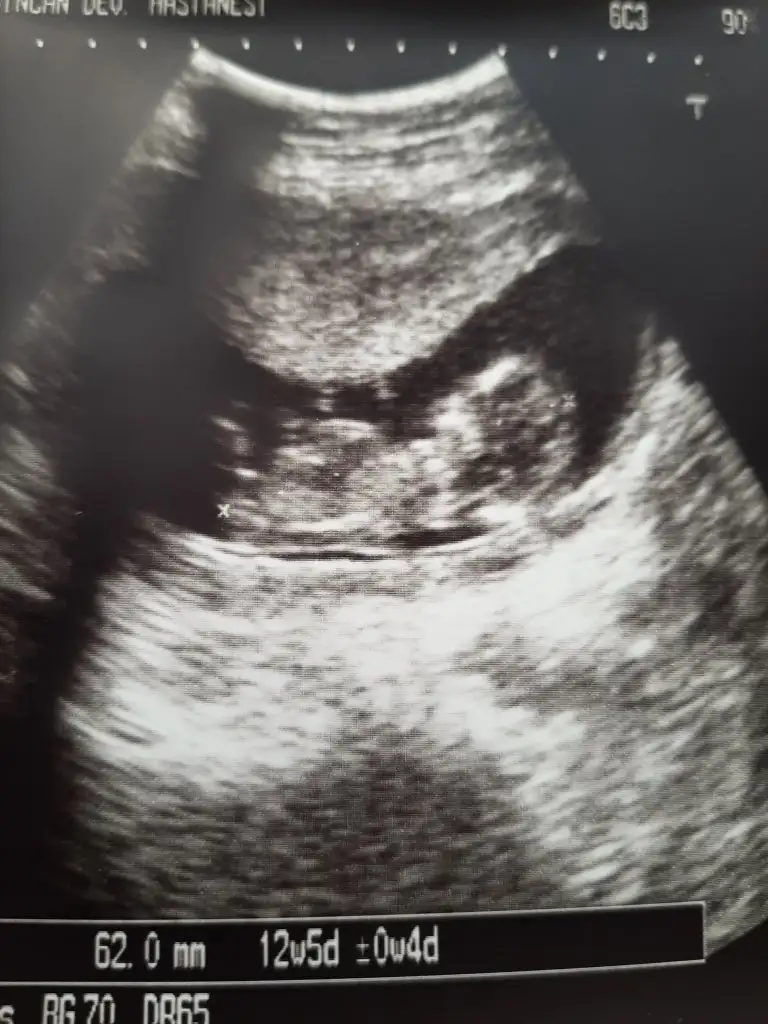

Dönüşünüz için çok teşekkür ederiz teyzesiErkek gibi sanki eninde olamadim çok karanlık nubu sanki biraz bir diklik var umarım u nubtur![]()

%60 diyelim emin olamadım cnmDönüşünüz için çok teşekkür ederiz teyzesiNub neresi onu da anlayabılsem

Kesinlik kazanınca bende anketı onaylayacağım Yüzde kaç erkek veya kız duruyor sizce ?

Bence kesinlikle erkek. Nubunda istif varBunlar var bir de..

Yüksek ihtimal erkek

Yüksek ihtimal erke